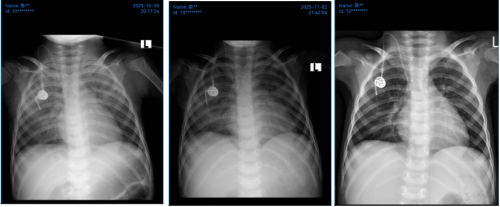

患儿胸片(10月30日,11月2日)